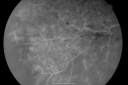

49-year-old woman has central retinal vein occlusion right eye with fluctuating vision and then recently her vision declined and she developed macular edema. I was worried about her angle and you were kind enough to do a peripheral iridotomy and I am dilating her today. Her vision is still poor. VISUAL ACUITY: OD 20/100. IOP: OD 20. There is a peripheral iridotomy, lens is clear, there is no rubeosis. EXTENDED OPHTHALMOSCOPY: OD: Vertical C/D ratio is 0.1. There is 2+ optic nerve edema, 3+ cystoid macular edema. The retinal veins are dilated in all 4 quadrants. The photos confirm clinical findings. Fluorescein angiogram shows some substantial delay in the venous circulation time with no non-profusion. IMPRESSION: 1. PERFUSED CENTRAL RETINAL VEIN OCCLUSION RIGHT EYE. 2. MACULAR EDEMA IN THE RIGHT EYE. DISCUSSION: I explained to the patient that with intravitreal Kenalog there is about an 80% chance of drying up the macula and improving the vision. There is a risk of cataract and glaucoma and a very low risk of infection. I injected the eye today without difficulty with the Kenalog.